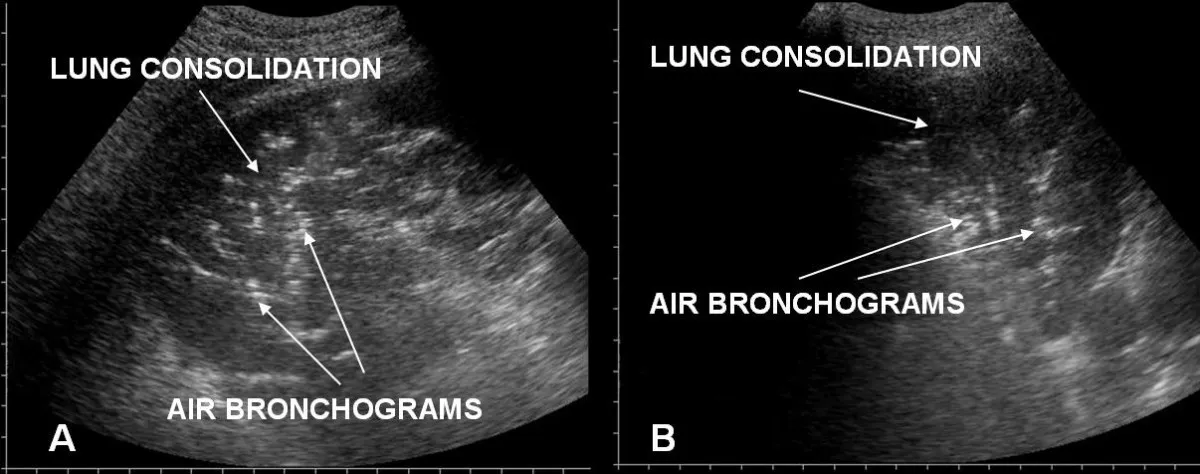

5. Static vs Dynamic Air Bronchogram with Real Case Video By Dr. Aisha Khan

Dr. Aisha Khan delivers a case-based, video-driven explanation of static vs dynamic air bronchograms — an absolute must-watch for residents aiming for conceptual clarity.

📌 What you’ll learn:

➡️ What is an air bronchogram?

➡️ Static vs dynamic air bronchograms — how to identify each

➡️ HRCT and lung ultrasound correlation

➡️ Obstructive atelectasis vs pneumonia

➡️ Real-time ultrasound case interpretation